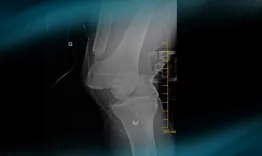

A professional rugby player who underwent ACL reconstruction with fascia lata (Mc FL) a few years ago​, presents with knee torsional trauma. After looking at the X-ray, MRI and pre-op testing, what can you say about this multiligament knee injury? What's the best course of action and how would you approach this case?

Management of a multiligament knee injury in a high-level pivoting sport athlete

Etienne Cavaignac